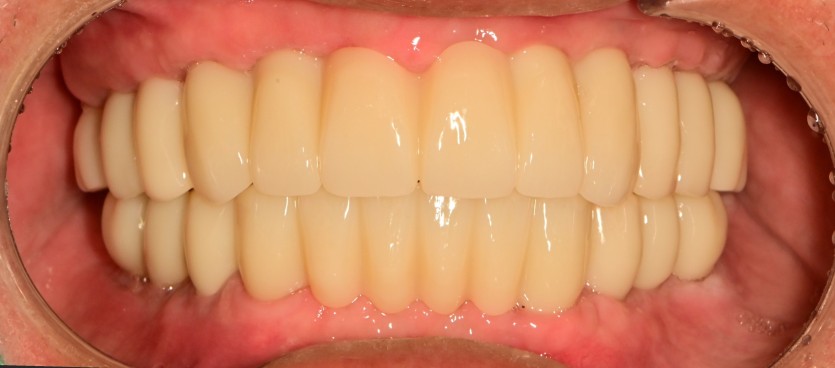

전체 임플란트 증례입니다.

18개의 임플란트로 완성하였습니다.